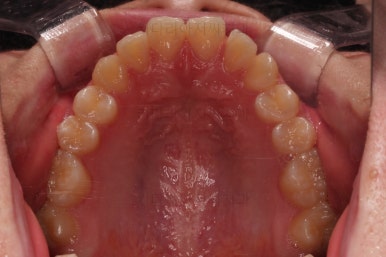

동래교정치과 초진 시 입안의 모습입니다.

치아가 벌어진 것도 벌어진 것이지만 교합이 전혀 안되고 있었어요.

틈새도 아랫니에 훨씬 많았고요.

윗니가 있는 위턱뼈가 전반적으로 아래턱에 비해 3차원으로 작은 양상이었습니다.

이번 환자분은 아랫니가 전반적으로 앞이든, 뒤든, 양옆으로든 넓어져 있는 양상이었고 그래서 아랫니에 틈도 많고 아래 앞니도 밀려나와 있는 양상인거죠.